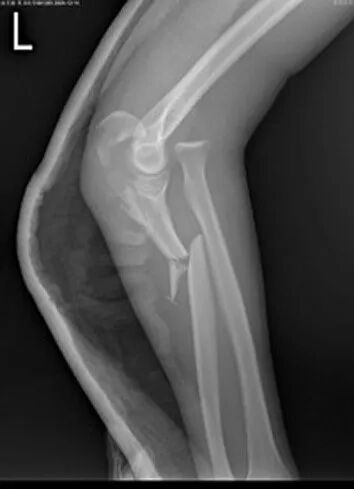

物理学改善我们生命的质量。仅就热力学现象的认识所带来的温度的概念和温度测量的实现,就不知道挽救了多少生命。光学成像原理的研究让许多人的视力问题得到精确的校正。X射线透视让骨骼损伤、肺结核之类的组织变异一目了然,而近些年才普及的X射线CT扫描、核磁共振等技术则让诊断具有无损、精确、多维等特点(图3),让发生在颅脑部、椎体部等活检取材不易或不可能的疾病得以快速诊断。此外,分子水平上的药物设计和制造得以实现的关键物理技术是大质量探测范围的质谱仪。在各种物理学设备更多地进入疾病诊断领域的时代,显然对医生进行充分的物理学培训(从设备原理的角度)是必要的。2007年发生在杭州的记者到几家医院踢馆的事件,反映的基本事实是,现代医生对其使用的诊断仪器显然缺乏起码的认识。